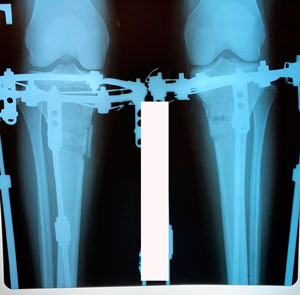

на фиксации

Вложения

image-01-04-20-01-07-3.jpg

image-01-04-20-01-07.jpg